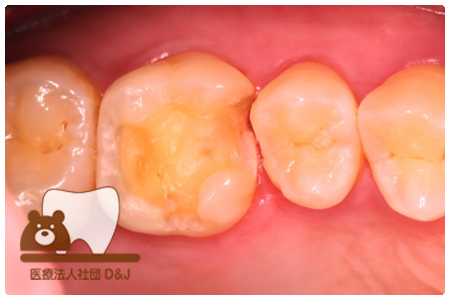

症例8フルジルコニアクラウン

治療前

治療中

治療後

29歳 女性

- 治療内容

- 銀歯からフルジルコニアクラウンへの修復

- 治療期間

- 根の治療含め3か月

- 費用

- 自費

フルジルコニアクラウン:77,000円(税込)

- その他の治療の費用は含まれておりません。

- リスク・副作用

- 強い衝撃が加わると欠けたり割れたりする可能性があります。また、噛み合わせの状態によっては脱離や周囲の歯への影響が出ることもあります。